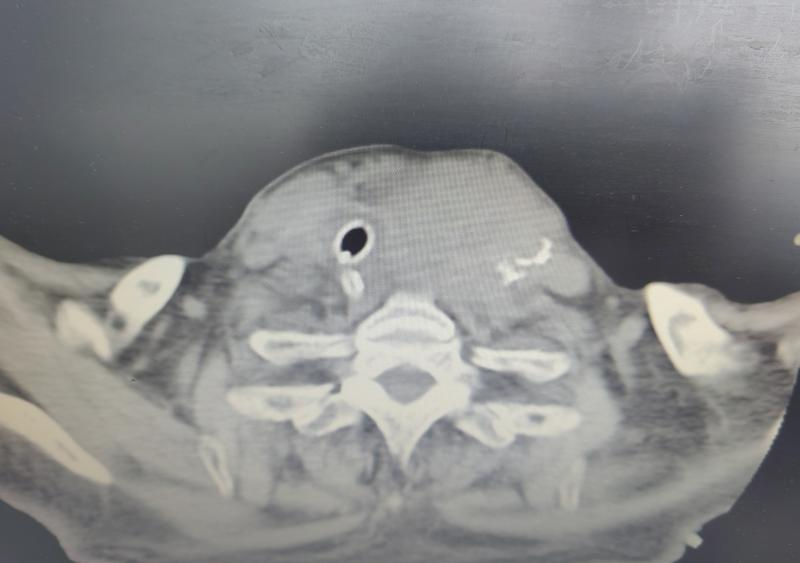

患者入院后,经详细询问病史并完善相关检查,耳鼻咽喉头颈外科医师团队会诊,认定患者为甲状腺左叶巨大肿物压迫气管导致呼吸道梗阻,需尽快手术治疗,切除甲状腺左叶,解除气道梗阻。

5月21日,耳鼻咽喉头颈外科副主任医师郑建军及主治医师田红,与麻醉手术科等相关科室相互配合,为患者实施手术。术中可见甲状腺左叶肿物大小约15×8cm,主体位于锁骨下方,与周围组织粘连,气管、食管受压右偏。因甲状腺肿物巨大,且与周围组织粘连,手术难度大,风险高,术中需谨慎操作,防止损伤颈部大血管及神经,给患者造成不可挽回的伤害。